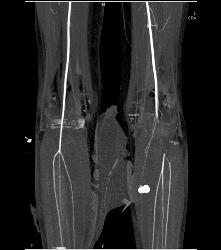

CTA Runoff With Occluded Left Popliteal Artery